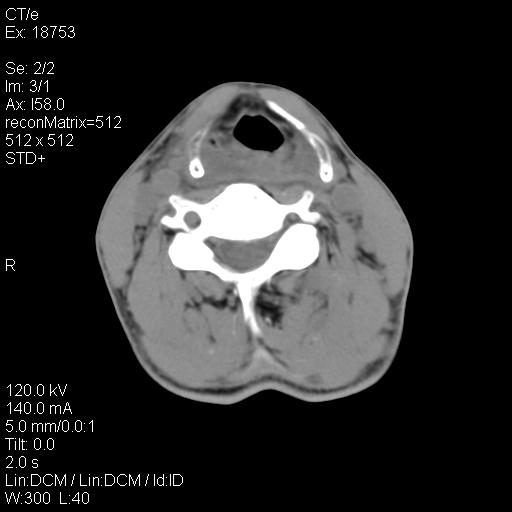

标题: CT21693:男 58岁 右侧咽部疼她2天余 PE:右侧扁桃体肿大 压痛 [打印本页]

标题: CT21693:男 58岁 右侧咽部疼她2天余 PE:右侧扁桃体肿大 压痛

右化脓性扁桃体炎症伴咽后壁脓肿形成.

1 弥漫性肿胀,与周围组织分界清晰,发病急,有明显症状,考虑急性炎症【wbc]

弥漫性肿胀,与周围组织分界不清,发病急,有明显症状,考虑:感染性病变!